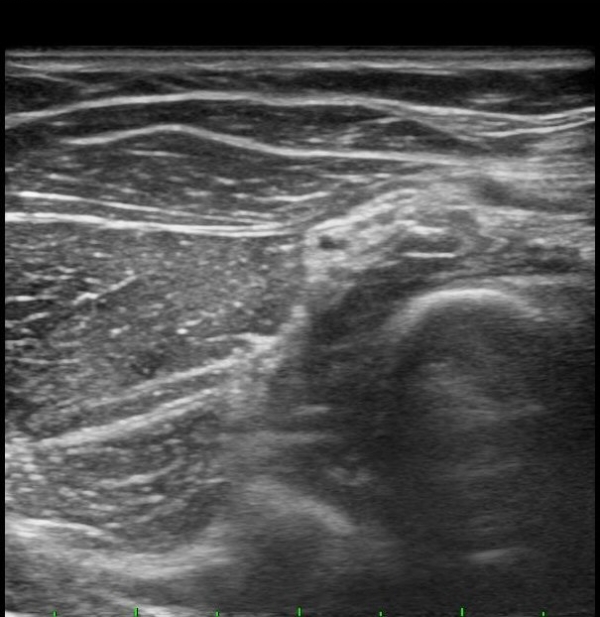

ÆÈ²ÞÄ¡ ¾ÕÂÊ È¾´Ü¸é°Ë»ç¿¡¼­ Èİñ°£½Å°æ(PIN)ÀÌ ¿ä°ñµÎ Àü¹æ¿¡¼­  Á¤»óÀûÀ¸·Î °üÂûµÊ(±×¸² 1).